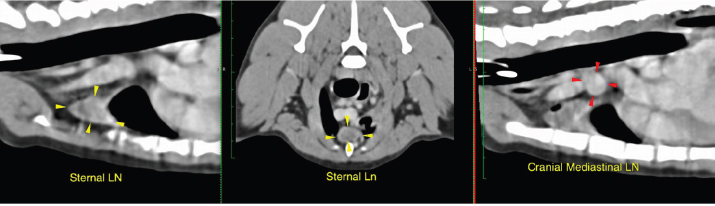

Plain and contrast CT studies of the thorax and abdomen were evaluated by a board-certified radiologist. A large, lobulated mass lesion on the left cranial lung lobe was identified that measured 7.6 × 2.1 × 5.8 (L × W × H) cm and extended to the level of the left main stem bronchus (Fig. 2). The mass surrounded, compressed and distorted all of the bronchi within the cranial subsegment of the left cranial lung and exhibited heterogeneous contrast enhancement with a few non-enhancing fluid pockets. At the right cranial and middle lung lobe, there was irregular nodular thickening which infiltrated into the lumen of the lobar and secondary bronchi, distorting the contour of the airway and causing near complete occlusion and distortion of the airway (Fig. 2). Similar irregular soft tissue thickening was identified in the lobar bronchus of the right middle lung lobe, extending through the distal branches and causing complete occlusion and distortion of the airway (Fig. 2). The sternal lymph node was moderately thickened, measuring approximately 1.1 cm in thickness (Fig. 3). The distinction between the sternal lymph node and the left cranial pulmonary mass was difficult, and it is possible that there was a direct invasion of the mass through the mediastinum pleura. A cranial mediastinal lymph node was moderately thickened and rounded, measuring approximately 1.0 cm (Fig. 3). Remaining lung lobes were well-inflated with no additional soft tissue lesions. CT scan of the abdomen was unremarkable.

Fig. 3. CT scan of the thorax showing enlarged sternal and cranial mediastinal lymph nodes.